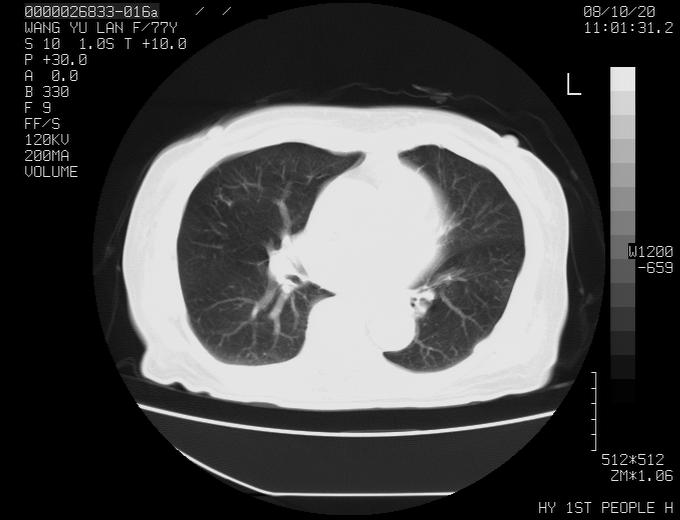

女性,77岁,胸部疼痛半月。左上肺团块影,本人考虑血管畸形,请分析

左上叶前段多发结节肿块并前段支气管息肉样结节、上叶腋亚段阻塞性肺炎,以结核可能性大。

纵隔有多个淋巴结肿大,提示周围型肺癌并转移可能性大。

动脉期未见大血管同步强化,首先考虑周围型肺癌